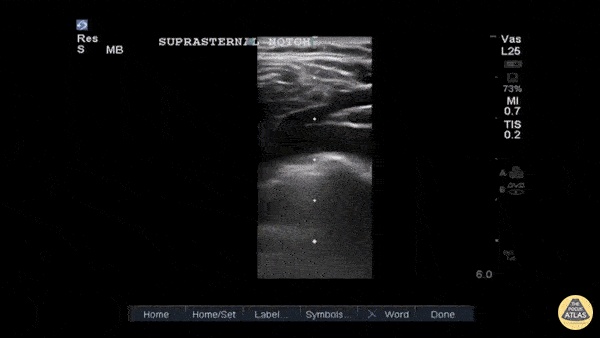

Thoracic Aortic Dissection & Aneurysm - Type B Thoracic Aortic Dissection Flap on Suprasternal View

This is a suprasternal notch view demonstrating an aortic flap in a patient with a Stanford Type B thoracic aortic dissection. This 40ish year old was a truck driver with untreated hypertension with sudden onset interscapular pain that migrated to his lumbar area. He stopped, lost strength in his right leg and was transported to our ED. The POCUS allowed the CV surgeon to prepare while the confirmatory CTA and standard treatment were performed. Suprasternal notch imaging with the linear or fine parts probe in a patient with suspicious signs/symptoms allows for a more rapid diagnosis of thoracic aortic dissection. John E. Hipskind, MD, FACEP Clerkship Director ED, Kaweah Delta Hospital